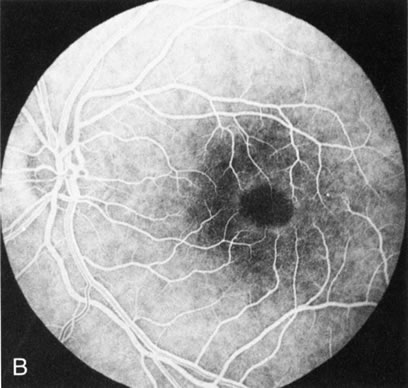

In CACD the bilateral macular lesions are solitary, circumscribed, and circular or ovoid in shape. They are unassociated with other findings such as drusen or flecks. FA will confirm the well-circumscribed area of choriocapillaris atrophy and further document that there are no associated findings that would lead to secondary choroidal atrophy in disorders such as age-related macular degeneration, Stargardt's fundus flavimaculatus, or dominant drusen of Bruch's membrane11 (Fig. 7 A and B).

Fig. 7. Central areolar choroidal dystrophy. The presence of choroidal atrophy in this well-circumscribed macular lesion (A) is confirmed by persistent visualization of the larger choroidal vessels as seen on angiography (B). Peripapillary (pericentral) choroidal dystrophy. The areas of choroidal atrophy are well-demarcated and contrast with the areas of normal choroid (C, D). Crystalline retinopathy (of Bietti). The areas of choroidal atrophy correspond to areas of the retina where crystals are not present (E, F).